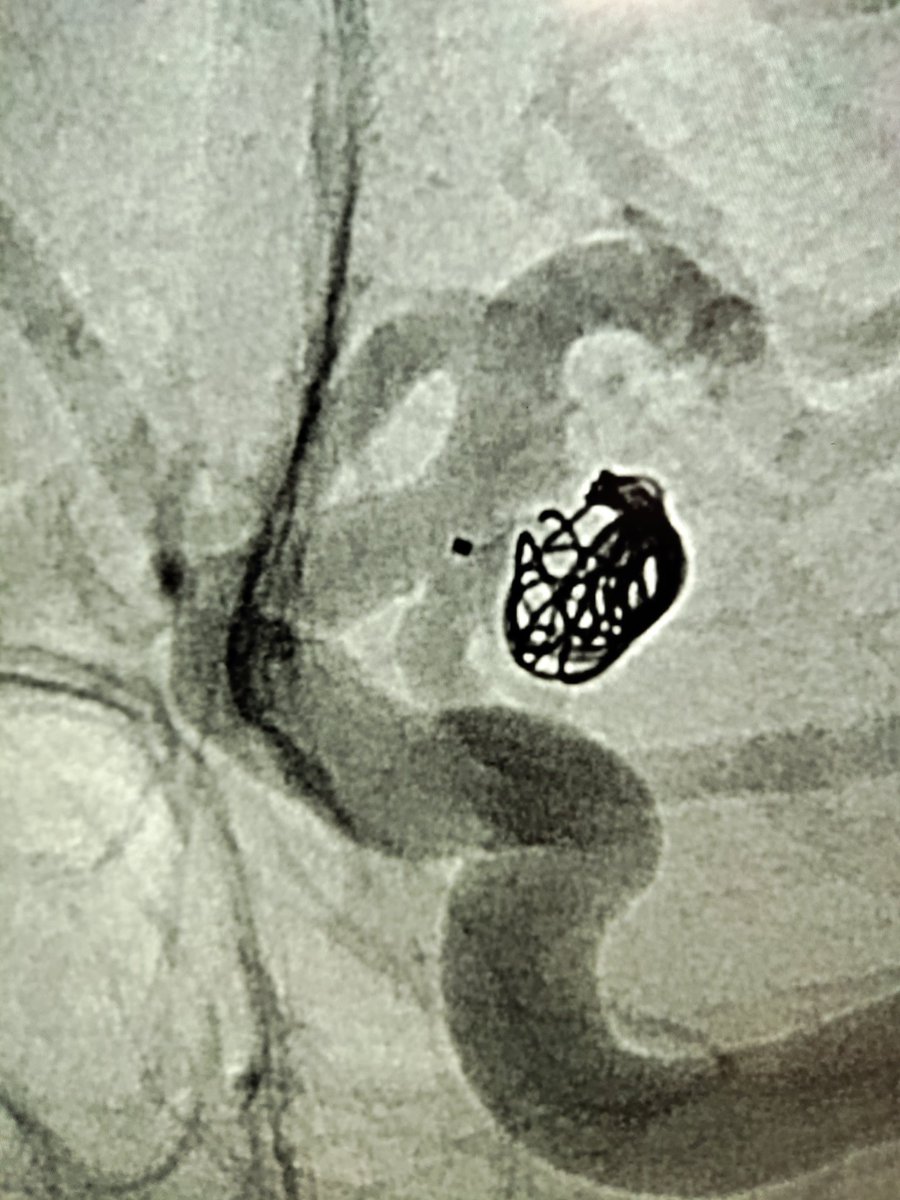

Wide-neck previously coiled/ruptured ACoA #aneurysm with bleb in neck. Perfect first Contour case in 2023 in the US🇺🇸 Cerus Endovascular Penn Neurosurgery #cerebrovascular CV Section #stasis #intrasaccular